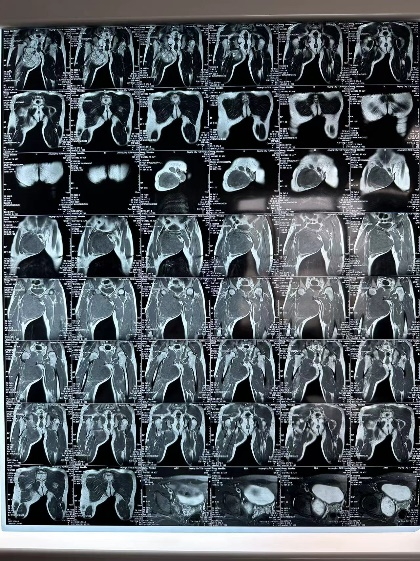

3D建模精准评估 MDT诊疗保驾护航

通过3D建模的精准评估,小王右耻骨软骨肉瘤体积达到了1600立方厘米(1600623.71立方毫米),肿瘤下极自右大腿中段向上,内侧贴大腿皮肤,外侧推压内收肌群及股动静脉,穿过骨盆右闭孔,紧贴右髋臼内侧壁生长,骨盆内占位部分推压膀胱。

图片 8.png图片 10.png图片 9.png

3d建模

患者的肿瘤累及右侧耻骨上下支(Enneking Ⅲ区),预计截骨范围为耻骨联合到耻骨上支、耻骨下支到坐骨体内侧。由于肿物体积巨大,无论采用髂股入路还是髂腹股沟入路,单纯前路手术很难暴露坐骨及髋臼后柱结构,而在前路强行提拉推压肿物则会增加肿瘤破裂的风险。通过延伸Gibson入路,可以清晰的显露坐骨支,完整地显露截骨边界,降低肿瘤破裂及血管损伤的风险。由于该部分区域为非负重区,因此,无需进行骨盆环重建,但需要注意盆壁的修补,预防盆腔器官受重力作用下垂相关并发症。